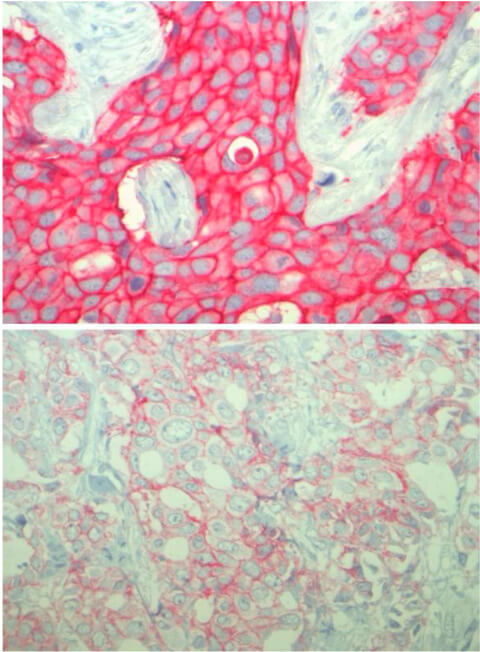

Der Tumor oben weist eine erhöhte Menge des HER2-Proteins auf, wohingegen der Tumor unten eine geringe Menge aufweist. Credit: Carsten Denkert Das wirkt sich insbesondere auf das Überleben der Betroffenen aus: „Wenn im Tumor das HER2-Protein in geringer Konzentration vorliegt, ist die Überlebenswahrscheinlichkeit der Betroffenen größer, als wenn das Gewebe gar kein HER2 enthält“, legt Loibl dar.

„48 Prozent dieser Gewebeproben zeigen eine schwach-positive Konzentration von HER2“, berichtet Denkert. „Wie wir herausfanden, lässt sich Tumorgewebe mit schwacher Positivität für das HER2-Protein als eigener Brustkrebs-Subtyp charakterisieren, der sich von Tumoren unterscheidet, die gar kein HER2-Protein aufweisen.“

Zugleich zeigen die Daten, dass Krebsformen mit wenig HER2 schlechter auf eine Chemotherapie ansprechen als Subtypen ohne HER2-Protein. „Offenbar ist Brustkrebs komplexer, als bislang angenommen wurde“, schlussfolgert Denkert. „Dies eröffnet neue Möglichkeiten für künftige, personalisierte Behandlungsansätze. In der Zukunft könnten neue Therapien, die sich speziell gegen niedrig-HER2-positive Tumoren richten, das Überleben in dieser Subgruppe noch weiter verbessern.“